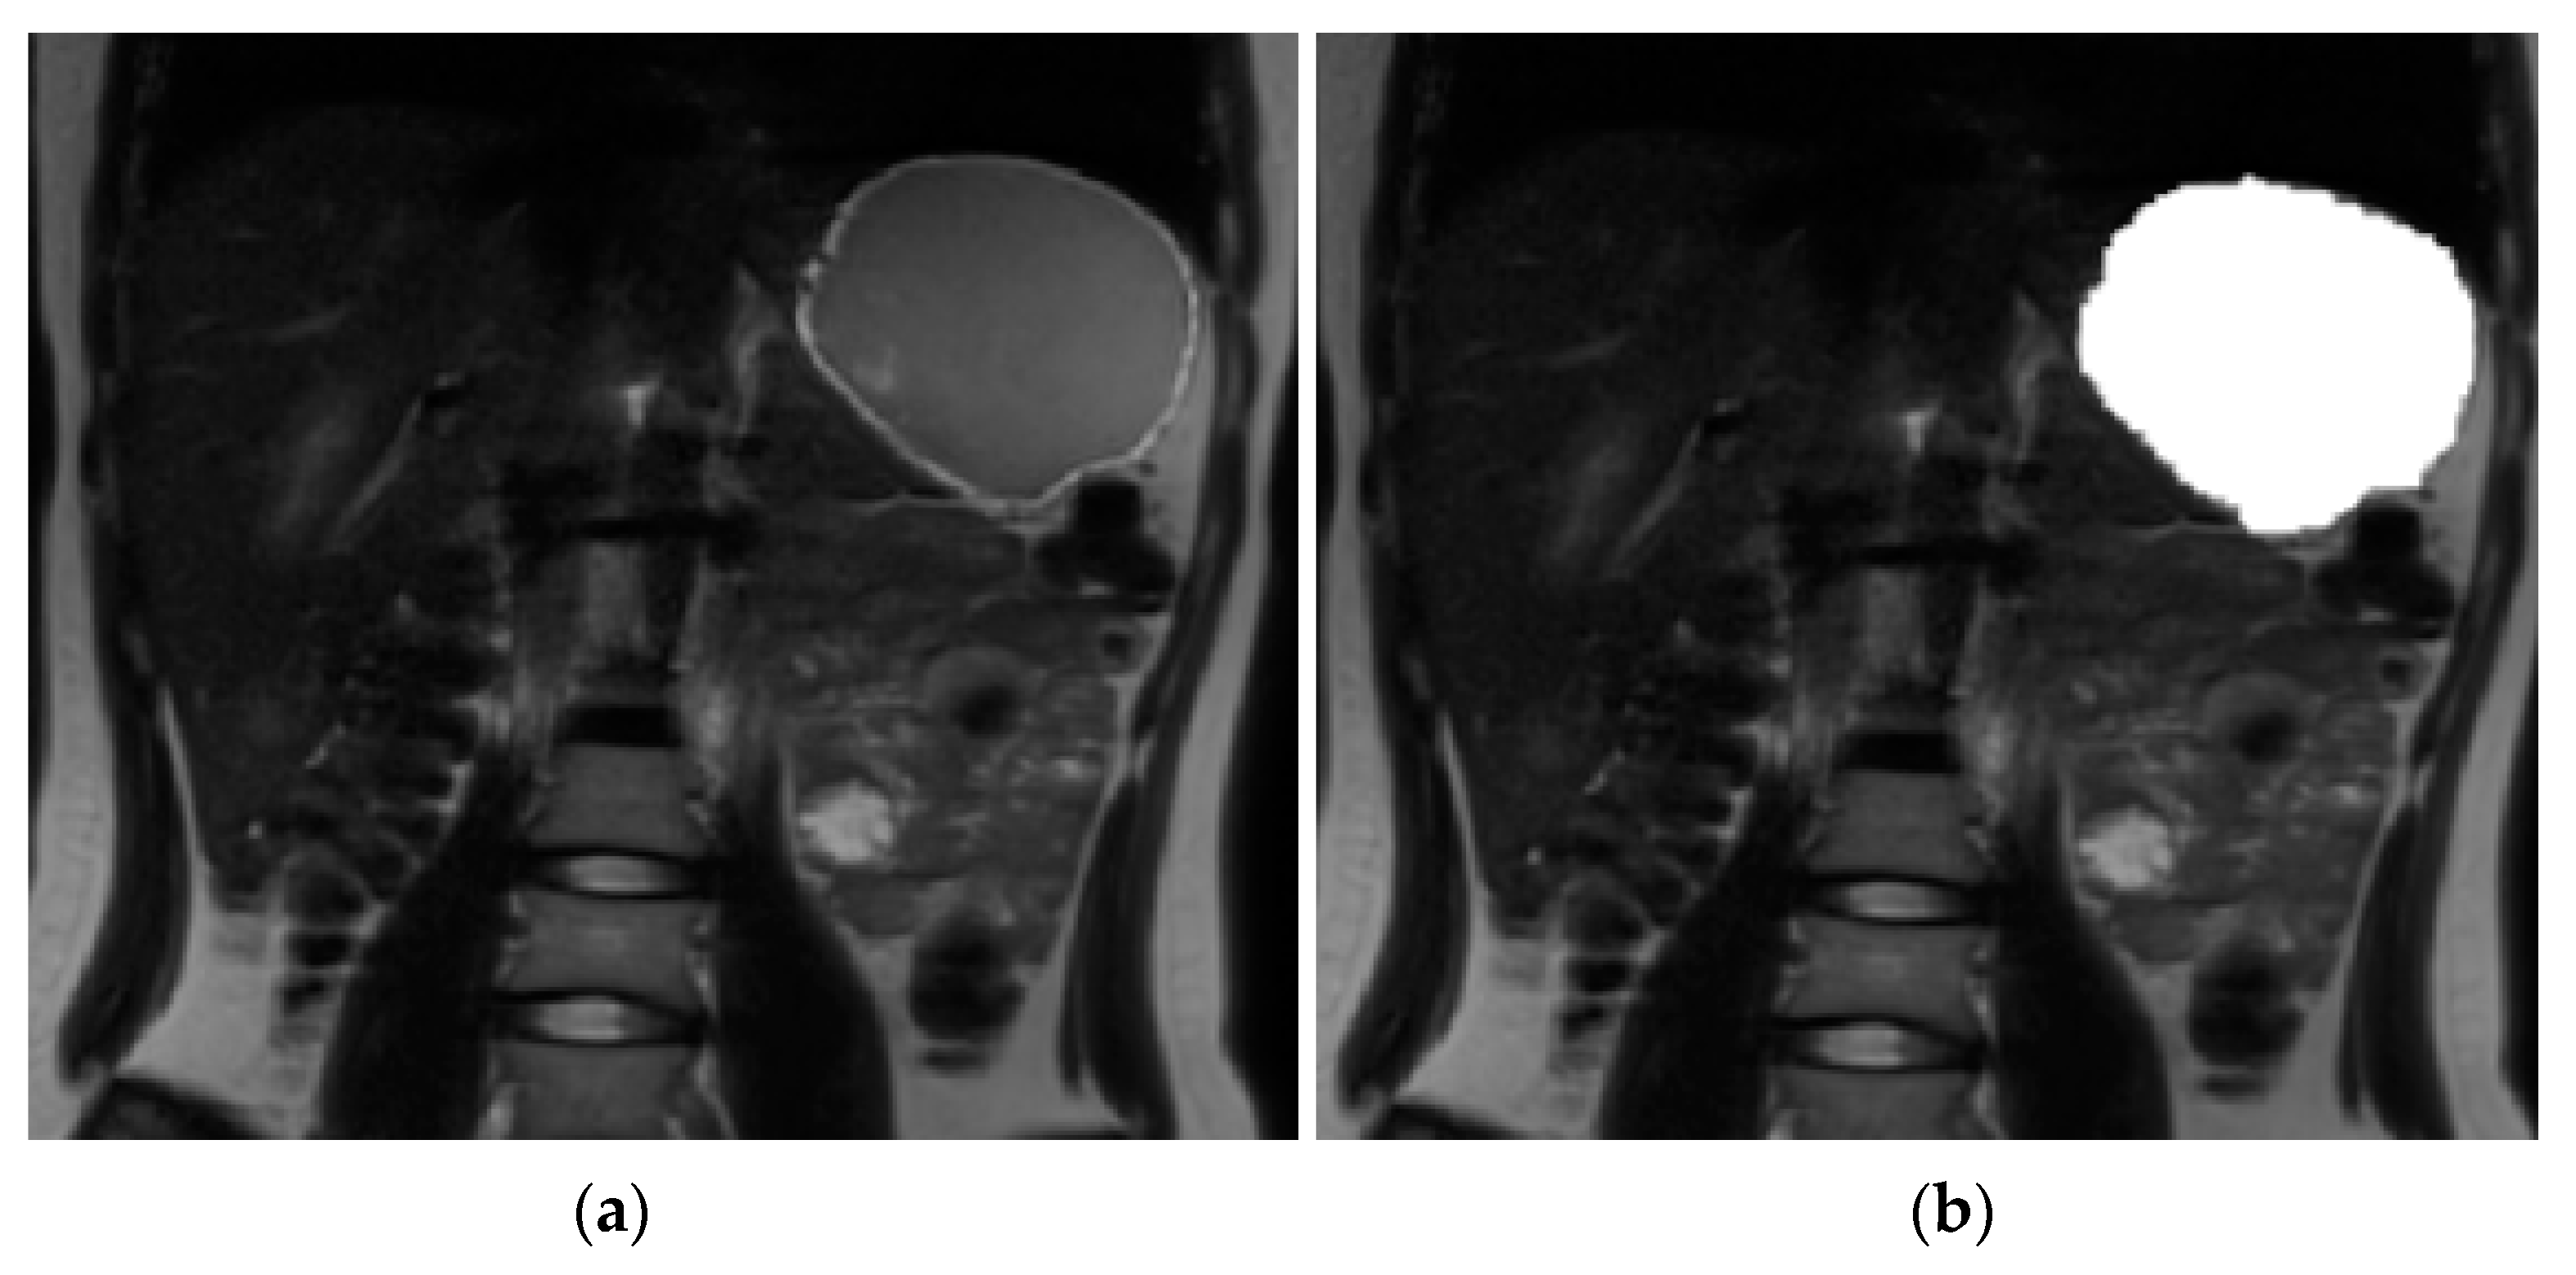

2.7. Image Analysis